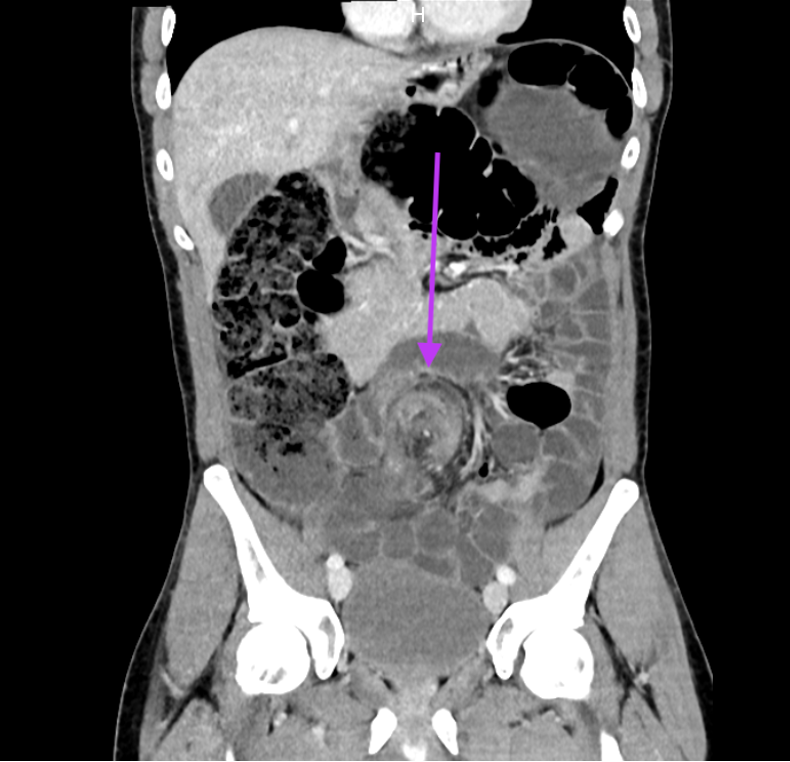

Ce scanner met en évidence un signe de Whirlpool (ou Whirl) qui représente la torsion du mésentère du sigmoïde et des vaisseaux mésentériques, diagnostic dans ce cas de volvulus du sigmoïde. On constate une dilatation en amont de l'ensemble du cadre colique et de quelques anses iléales avec stase colique importante, sans signes de souffrance intestinale.

Les occlusions basses représentent 25-35 % de l’ensemble des occlusions digestives, les causes principales étant le cancer colique, la sigmoïdite diverticulaire et le volvulus colique. Le volvulus du sigmoïde, 6% des occlusions intestinales, correspond à la torsion du sigmoïde autour de son méso avec un degré de rotation de 180 à 360° et touche essentiellement les sujets âgés, peu mobiles, constipés chroniques. Il existe des prédispositions anatomiques chez certains sujets (dolichocôlon : boucle sigmoïdienne longue, mobile, congénitale) et une prédisposition masculine.

Le scanner abdominopelvien est l’examen de premier choix avec une sensibilité proche de 100 % et une spécificité supérieure à 90 % et permet de rechercher les complications potentielles (ischémie ou perforation avec péritonite).